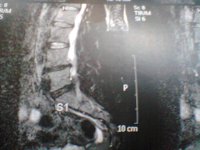

ich versuch es einfach mal...also ich hab seit ca 2 Jahren einen Bsv L4/L5 bislang ohne OP...

ich war 4 Wochen in reha danach habe ich die Wiedereingliederung gemacht und arbeite seitdem wieder in Vollzeit ( seit September 2011 ) jetzt seit 1 Monat habe ich wieder starke schmerzen und dazu gekommen ist mein Steißbein,kann kaum sitzen und beim aufstehen tut es höllisch weh

arbeiten geh ich zur zeit nur 5-7 Std danach geht nicht mehr.....nehme seit ca 7 Monaten Targin 20mg/10 mg 3 mal am Tag...so wirklich lange helfen die leider auch nicht mehr...Heute war ich beim MRT könnte jemand von euch mir die ein bissel beschreiben????